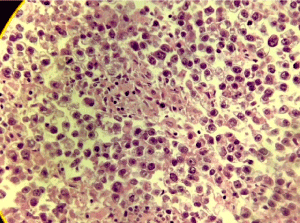

Figure 4. metastastasis nest with light cytoplasma, promient nucleoli, and central nucleus, case 2